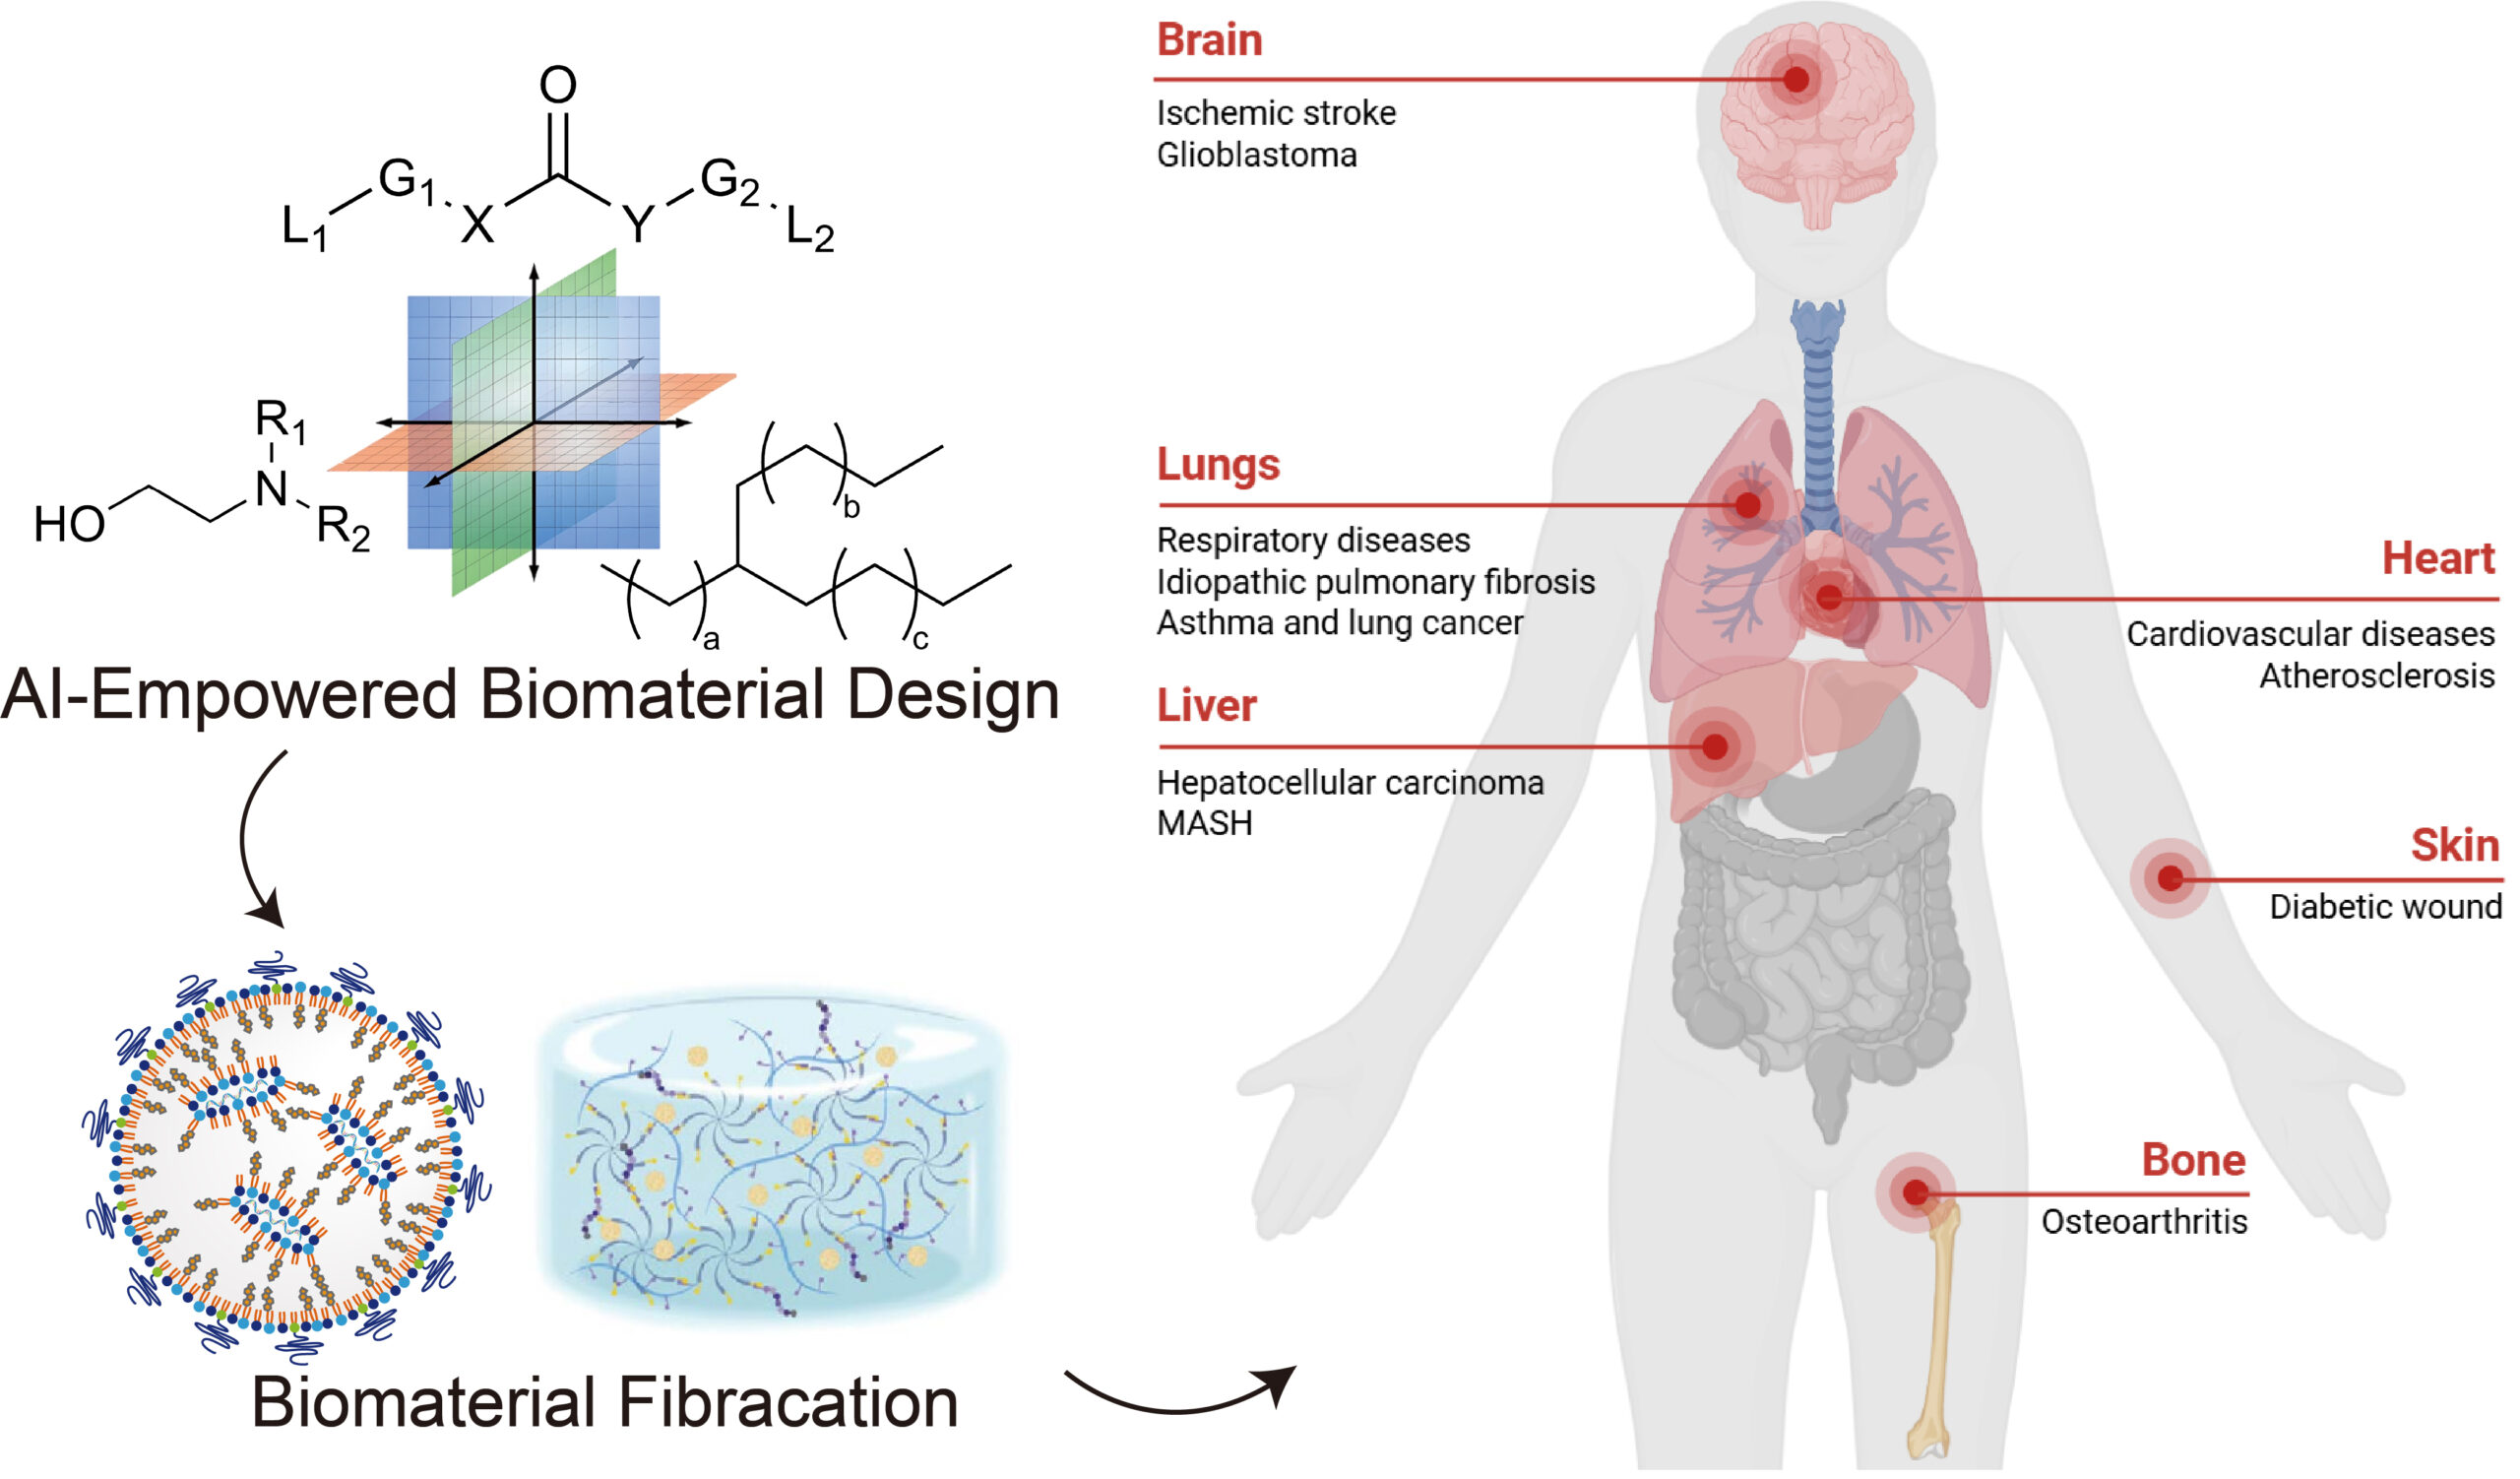

开发安全高效的核酸递送系统

推动 RNA 药物实现临床转化

研究领域:

(1)AI 赋能脂质分子与mRNA 序列元件的理性设计,探索脂质纳米载体体内递送过程,研发安全、高效、精确的RNA递送系统;

(2)针对肺靶向递送难点,构建新型吸入式RNA递送系统,为肺靶向核酸药物开发建立通用技术平台,为肺纤维化、哮喘、肺癌等呼吸系统疾病提供创新解决方案;

(3)研发新一代可编程可注射水凝胶多功能植入材料,达成药物或细胞因子体内时空精准递送,拓展其在再生医学领域的应用范围。

脂质理性设计

采用组合化学策略,基于可电离氨基、 疏水尾链及连接键的模块化设计,并引入人工智能(AI) 和创新化学合成方法,合成多功能脂质分子文库;制备具有高 RNA 包封率的脂质纳米颗粒(LNP),通过结构优化调控 LNP 与生物体系的相互作用,实现安全高效 LNP 或低肝富集型 LNP 等 RNA 载体文库的高效构建与筛选。

代表性论文:Journal of the American Chemical Society, 2025; ACS Nano, 2024; ACS Nano, 2022

吸入式肺靶向RNA递送系统

创新构建吸入式 RNA 递送系统实现呼吸疾病治疗机制突破:针对 LNP 雾化后粒径增大、 包封率下降及难以突破黏液屏障等难题,通过脂质结构、制剂创新和制备工艺的多维协同优化,构建兼具优异的雾化稳定性、气动性能与黏液穿透性能的吸入式递送系统,在多种呼吸系统疾病模型中展现出高效的基因调控和显著的治疗效果。

代表性论文:Nature communications, 2025;Nature communications, 2025; Nature Communications, 2024(ESI高被引论文); Science Advances, 2022(ESI高被引论文)

靶向型脂质递送系统

模块化脂质共组装策略实现靶向核酸递送及重大疾病治疗机制创新:提出“模块化分子组装”策略,设计具备靶向功能的脂质模块, 组装构建可高效定向递送至肝星状细胞、巨噬细胞、小胶质细胞等细胞的核酸载体;首次提出“正反馈增效”靶向递送机制,并在心脑血管、肝代谢等疾病动物模型中展现出显著的治疗效果,为重大疾病治疗开辟新路径。

代表性论文:Nature Communications. 2023; ACS Nano,2024; ACS Nano,2024; ACS Nano,2023; ACS Nano,2023